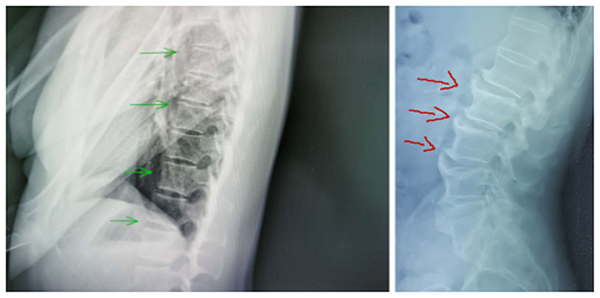

“弥漫性特发性骨质增生症”,一听这名字,就有种“不明觉厉”的感觉。弥漫性特发性骨质增生症多见于老年人,是影像学检查发现的一种以脊椎及脊椎韧带,特别是胸椎前缘及外侧韧带广泛骨化为主要特征的骨关节退变性病变。X线表现具有特异性,影像学表现至少有连续4个椎体的前外侧缘钙化或骨化,在椎间隙水平骨化带增厚隆起而使其成为波浪状,骨化带与椎体间可见一条透明带。

左图为正常骨质,右图为骨质增生。